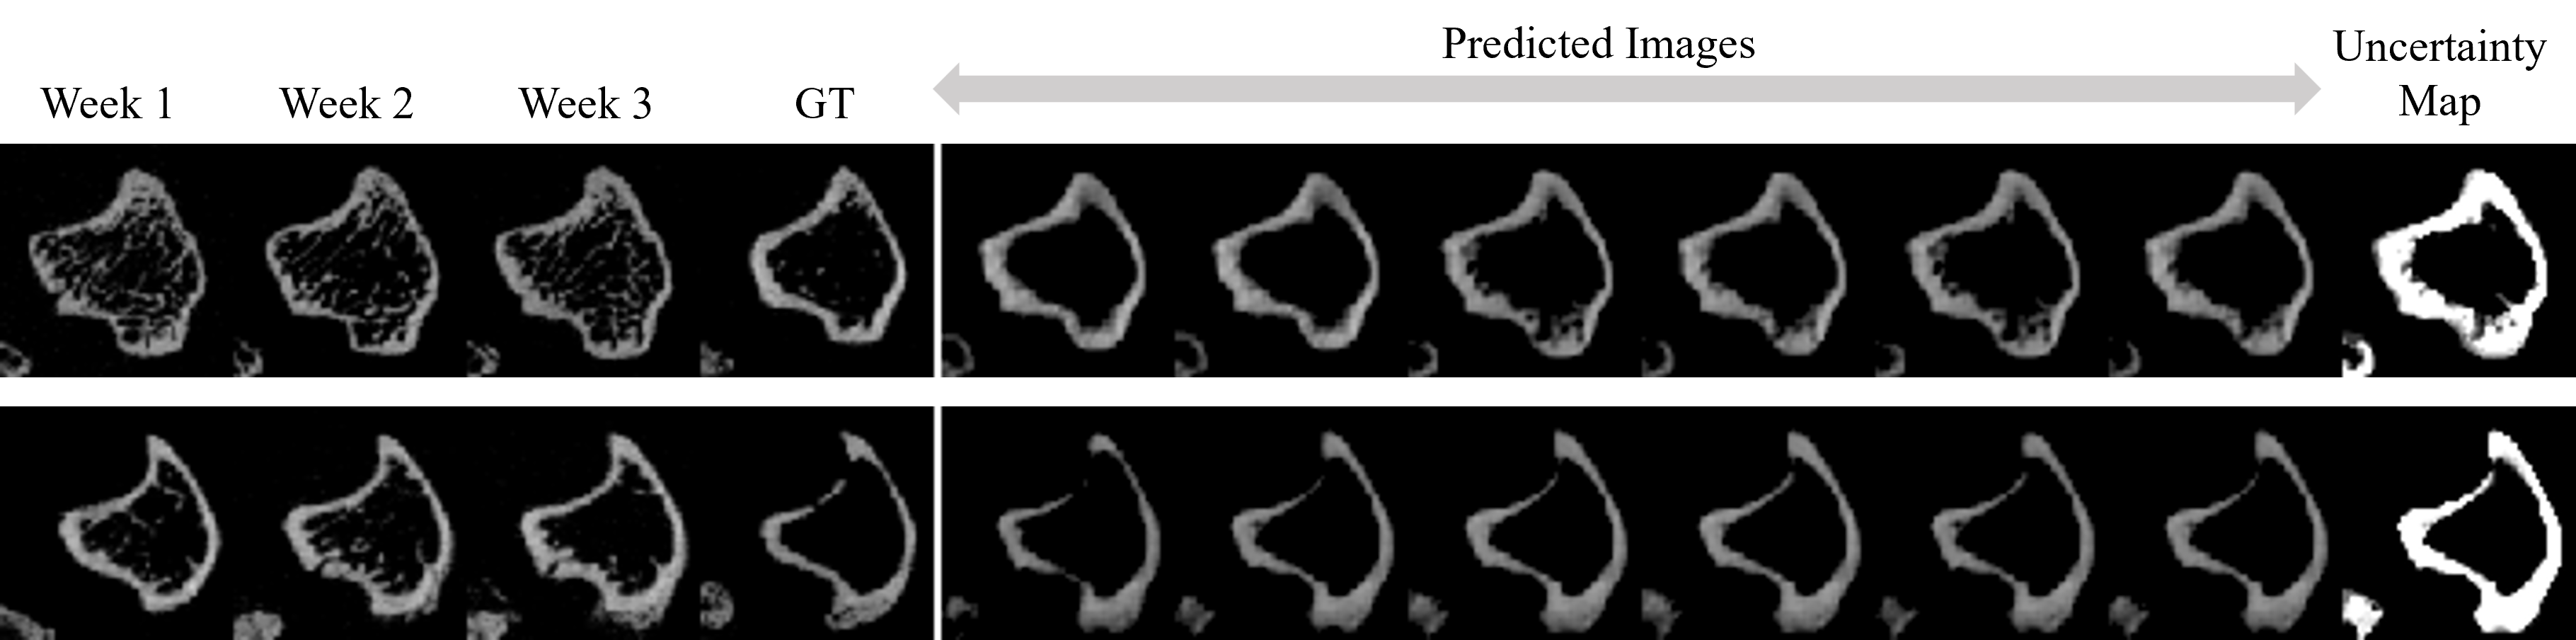

Refer to caption

Figure 4: In each row, we show the slices of the first three weeks, the ground-truth slice in the fourth week, six predicted slices by sampling various ztsubscript𝑧𝑡z_{t} of our model, and the uncertainty map of the predicted slices. We observe that the primary part of the image, i.e., the boundary of the bone (the tibial cortical bone) remains unchanged, while the other parts (the bone marrow regions) are diverse. Please zoom in to see the details of the predictions and the uncertainty map.

Our model contains a stochastic component that samples the latent vector ztsubscript𝑧𝑡z_{t} from an encoded latent distribution. Such a design is based on the stochastic nature of the progression of bone lesion. Given the bone slices of the previous weeks, there is still reasonable uncertainty on the bone state of the next week. The distribution intuitively reflects the range of plausible outcomes of the bone progression based off the previous weeks’ scans x1,x2,x3subscript𝑥1subscript𝑥2subscript𝑥3x_{1},x_{2},x_{3}. Depending on the choice of ztsubscript𝑧𝑡z_{t}, the constitution of the resulting prediction x4subscriptsuperscript𝑥4x^{\prime}_{4} can vary as shown in Figure 4. Interestingly, given different ztsubscript𝑧𝑡z_{t}, the boundary regions (the tibial cortical bone) of our predicted bone remain largely unchanged. Such regions are the key factors for a clinician to determine if there is lesion in the bone or not. In the meanwhile, different contents are generated in the non-boundary areas (the bone marrow regions), showing the diversity of our results.

Figure 4 also shows the uncertainty map of the diverse predictions. The intensity of each pixel in the uncertainty map indicates the probability of the predicted pixel in that location to be non-zero. From the uncertainty map we observe that pixels in the boundary regions show a very high probability, while pixels in the non-boundary regions show a lower probability, i.e., our model can capture the core temporal patterns and generate pixels with a very high confidence and low uncertainty in the important regions (boundary regions). Our model also enables the diversity by generating pixels with a relatively lower confidence (higher uncertainty) in the non-boundary regions.